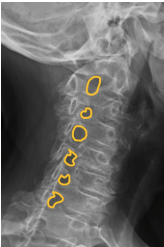

Lesão degenerativa discal

aonde estão as lesões nas imagens?

1. Lesão degenerativa discal de C5-C6- C7

2. Lesão degenerativa discal de L2-L3-L4-L5